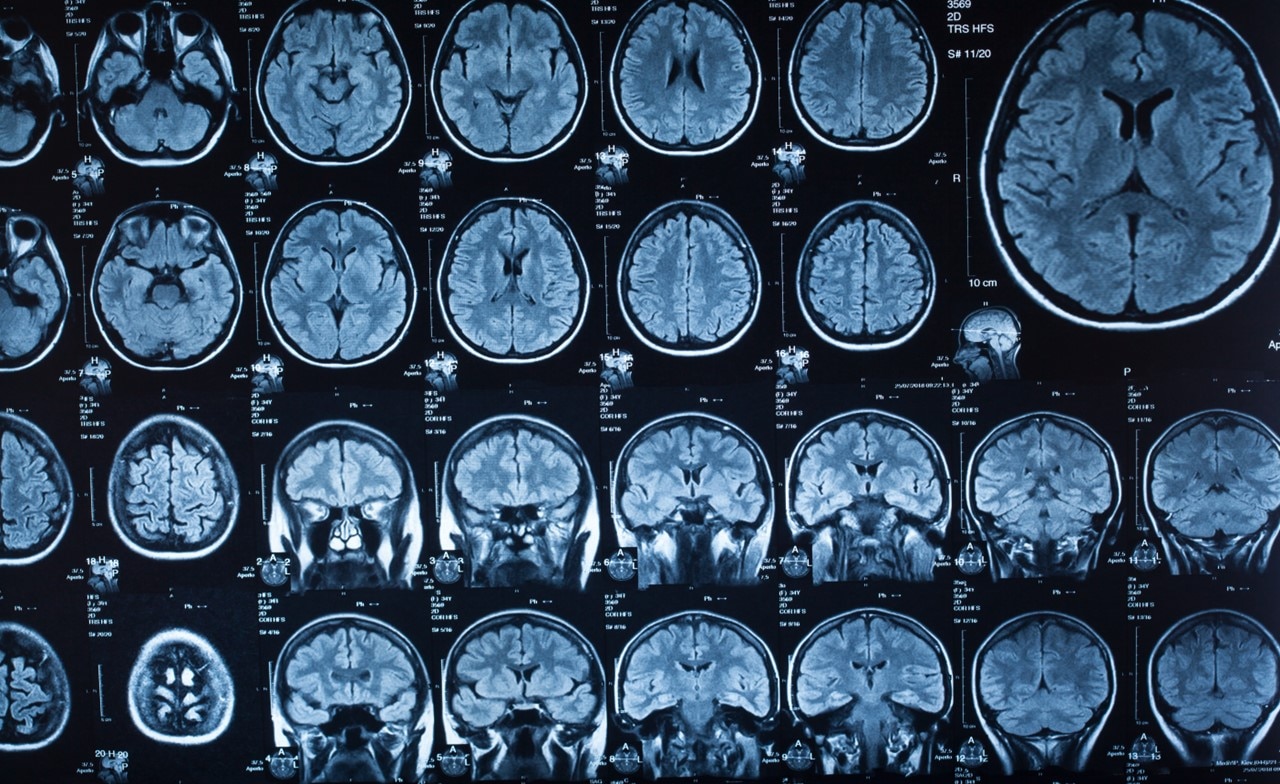

Pharmacological researchers at one of the world’s largest biotech companies had the arduous task of manually generating comprehensive scientific reports. The existing approach involved sifting through massive datasets of medical papers, synthesizing this information, and then crafting complex narratives. The manual nature of the process made it both time-consuming and prone to human error.

Existing software tools provided insufficient intelligent processing for such large datasets and was unable to generate reports that mirrored human-like comprehension and coherence. Maintaining the quality, coherence, and completeness of automated reports was a significant concern for our client.

- Report generation: The similar content was then fed into the large language model (LLM), which generated coherent and comprehensive reports. This approach, along with the client’s responsible AI policy requiring humans to conduct the final reviews, ensured highly accurate reporting, as it combined the capabilities of the LLM with the latest information—even if the LLM was not directly trained on it.

In collaboration with the client, our experts used CGI TextAI to boost efficiency by reducing the time to produce comprehensive reports from weeks to minutes. Additionally, users had the freedom to determine the sources and format of their reports, ensuring the output aligned with their requirements. The solution also increased the accuracy and coherence of the newly generated reports through the combined power of vector-based data retrieval and the LLM. By automating the data extraction and writing process, susceptibility to human errors, previously a major concern, was significantly reduced.